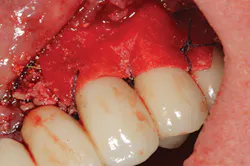

Peri-implantitis has been defined as an inflammatory process that affects the tissues around an osseointegrated implant in function and, like periodontitis, results in loss of supporting bone6 (Figs. 3 and 3a). The prevalence of peri-implantitis has been shown in some studies to range from 11% to as high as 47% of implant sites analyzed.(16) Most literature reviews agree that once bone loss has occurred around an implant, nonsurgical therapy is not as effective as surgical treatment.(17) Surgical intervention by the dentist or specialist includes raising a full thickness flap around the affected dental implant in order to completely expose the dental implant surface (Fig. 4). Mechanical debridement with hand and high-speed instrumentation as well as irrigation with various medicaments is advocated in order to detoxify the implant surface and alleviate bacterial contamination. After decontamination, the flap can be apically or coronally positioned. In addition, various regenerative technologies, including bone and soft-tissue grafts, growth factors, and barrier membranes have been used to rebuild lost tissue support around the dental implant (Figs. 5 and 5a). Different methods of guided bone regeneration around implants affected with peri-implantitis were demonstrated, and the results have been shown to be stable for a follow-up period of up to seven years.(18) That being said, no gold standard of peri-implant disease has been documented and "available evidence does not allow specific recommendations for the therapy of peri-implantitis."(19)